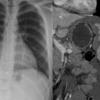

Cardiac torsion post BCT

pre-torsion